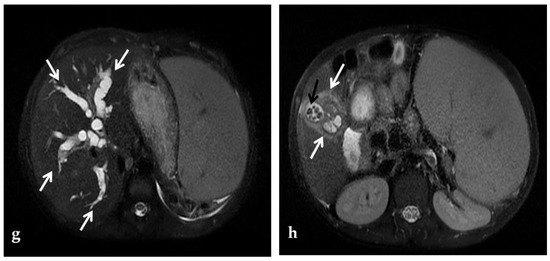

Portal biliopathy is defined as the presence of abnormalities of the extrahepatic and intrahepatic bile ducts and gallbladder walls in patients with noncirrhotic/non-neoplastic PVT [2] (Figure 2).

CDUS, CT, and MR images of a 9-year-old male with intrahepatic and extrahepatic cavernous transformation of the portal vein and portal biliopathy who presented with jaundice and cholangitis. (a) A Color-Doppler Ultrasound image shows multiple collateral vessels at the porta hepatis (arrows) and the absence of the main portal trunk. (b) Spectral evaluation of the major collateral vein of the cavernoma shows an hepatopetal flow with a velocity within normal ranges, which could potentially be misleading by an unexperienced operator. (c) An ultrasound image scan through the gallbladder shows a mildly echogenic endoluminal stone in the gallbladder (arrow). (d) Color-Doppler Ultrasound image shows multiple dilated collateral cavernous vessels in the gallbladder fossa (arrow). (e) Portal phase axial CT image shows dilation of intrahepatic biliary ducts (arrow) due to extrinsic compression of the common biliary duct by the cavernoma. (f) A caudal axial CT view in the portal venous phase shows a mildly hyperdense stone in the gallbladder (white arrow) which is surrounded by dilated cavernous vessels (black arrow). (g) Axial T2-weighted MR image shows intrahepatic biliary dilatation (arrows) due to common biliary duct extrinsic obstruction by prominent paracholedochal collateral cavernous vessels. (h) A caudal axial T2-weighted MR view shows wall thickening of the gallbladder (white arrows) which contains other multiple small gallstones in the fundus (black arrow).